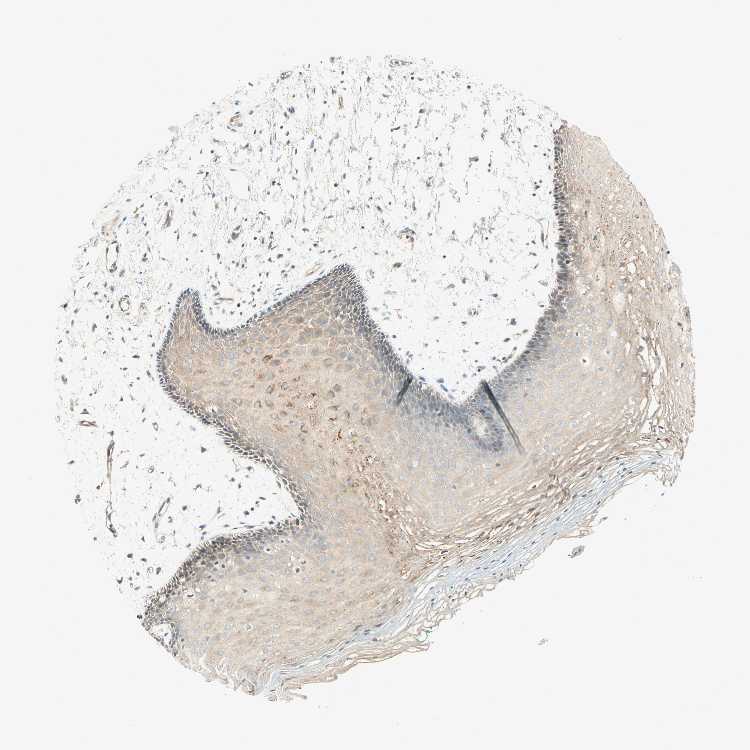

TISSUE PRIMARY DATA ORAL MUCOSA Show tissue menu

ORAL MUCOSA - Antibody stainingi

Antibody staining in the annotated cell types in the current human tissue is reported as not detected, low, medium, or high, based on conventional immunohistochemistry profiling in selected tissues. This score is based on the combination of the staining intensity and fraction of stained cells.

Each image is clickable and will lead to virtual microscopy that enables deeper exploration of all samples and also displays staining intensity scores, fraction scores and subcellular localization as well as patient and tissue information for each sample.

Antibody HPA007047Antibody HPA007456Antibody CAB025274

Squamous epithelial cells LowMediumNot detected